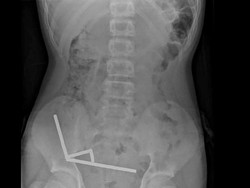

Penampakan Ngeri Usus Anak 13 Tahun usai Telan 100 Magnet, Berakhir Dioperasi

Anak 13 tahun di Selandia Baru terpaksa kehilangan sebagian besar ususnya pasca menelan mainan magnet berkekuatan tinggi. Bagaimana nasibnya?